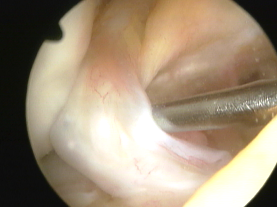

Mikrofrakturierung:

Im Rahmen einer Gelenkspiegelung (Arthroskopie) wird der unter dem Knorpel liegende Knochen mit speziellen Ahlen oder Bohrern eröffnet. Das Blut, das den Defekt füllt, enthält körpereigene Reparaturzellen (sog. Stammzellen). Nach ca. 6 Wochen ist die Defektzone mit Knorpelersatzgewebe ausgefüllt. Zur Sicherung des OP-Erfolges ist eine Teilbelastung des operierten Beines für einen Zeitraum von 6 Wochen erforderlich.